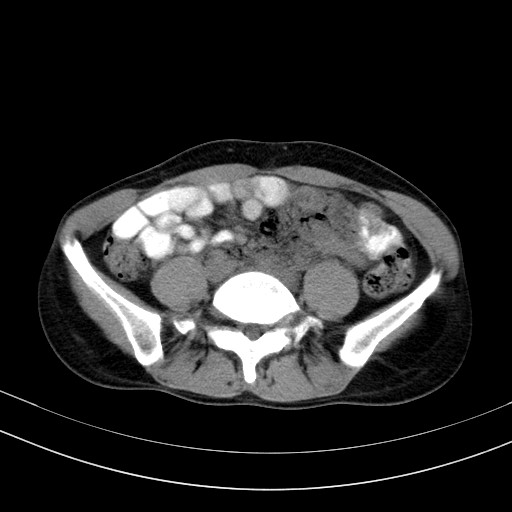

以下是引用随光逐影在2009-4-7 8:17:00的发言:[br]考虑宫颈占位性病变(宫颈癌?);建议行进一步检查。

以下是引用jiangjing在2009-4-7 16:46:00的发言:[br]宫颈增大,结构不清,右侧附件区可疑囊样占位,建议增强及mri 检查